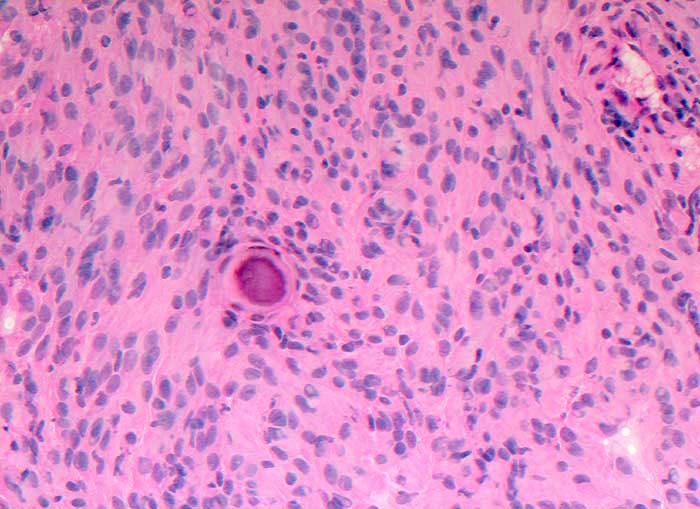

Meningeom

Im Schnellschnitt sind psammomatöse Verkalkungen und meningotheliale Zellen ohne Atypien erkennbar.

Zytologische Diagnose: Meningeom. Am ehesten handelt es sich um einen transitionalen Typ mit häufigem Nachweis von Wirbelbildungen und Psammomkörperchen.